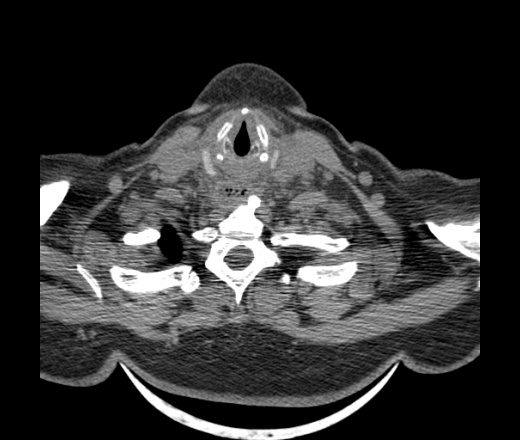

Женщина поступила в х/о спустя 4 дня после того как при употреблении карася подавилась костью.

Наличие газа в средостении на протяжении тел С2-С6 (медиастинальна эмфизема); рыбная кость на уровне тела С6.

При всем уважении, но говорить о медиастинальной эмфиземе, оценивая мягкие ткани шеи, как-то слишком резко. На мой взгляд, это ретрофарингеальное пространство.

Эвакуировали почти 100мл гноя. Но кость не смогли найти. Думаю что она даст дальнейшее ослоднение. Эндоскопически за черпалонадгортаной звязкой не смогли зайти в пищевод, все мягкие ткани отечные, просвет пищевода сдавлен. По всей видимости параэзофагеальная клетчака тоже задействована. Эмпиема, если ее можно так назвать, незнаю как правильно дошла до уровня яремной вырезки. Чем закончиться напишу. Ждем медиастинита.

Согласен с Вами; конечно, наличие газа в клетчатке ретрофарингеального пространства (затмение с опечаткой..). К сожалению, процесс "продвигается" к медиастиниту. Но почему никто, не отмечает наличие рыб. кости; или это для Всех очевидно?

Кость то мы сразу выявили, размеры где то 17*2мм, но ее так и не получается найти в этой каше